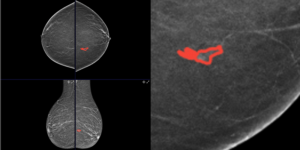

- Gold-Standard Modality: All images utilize Digital Breast Tomosynthesis (DBT) also known as 3D Mammography.

- Focus on Early Detection: With an average tumor size of just 1.34 cm, the dataset is uniquely suited for training AI models on subtle, early-stage findings. Approximately 85% of lesions are smaller than 2 cm.